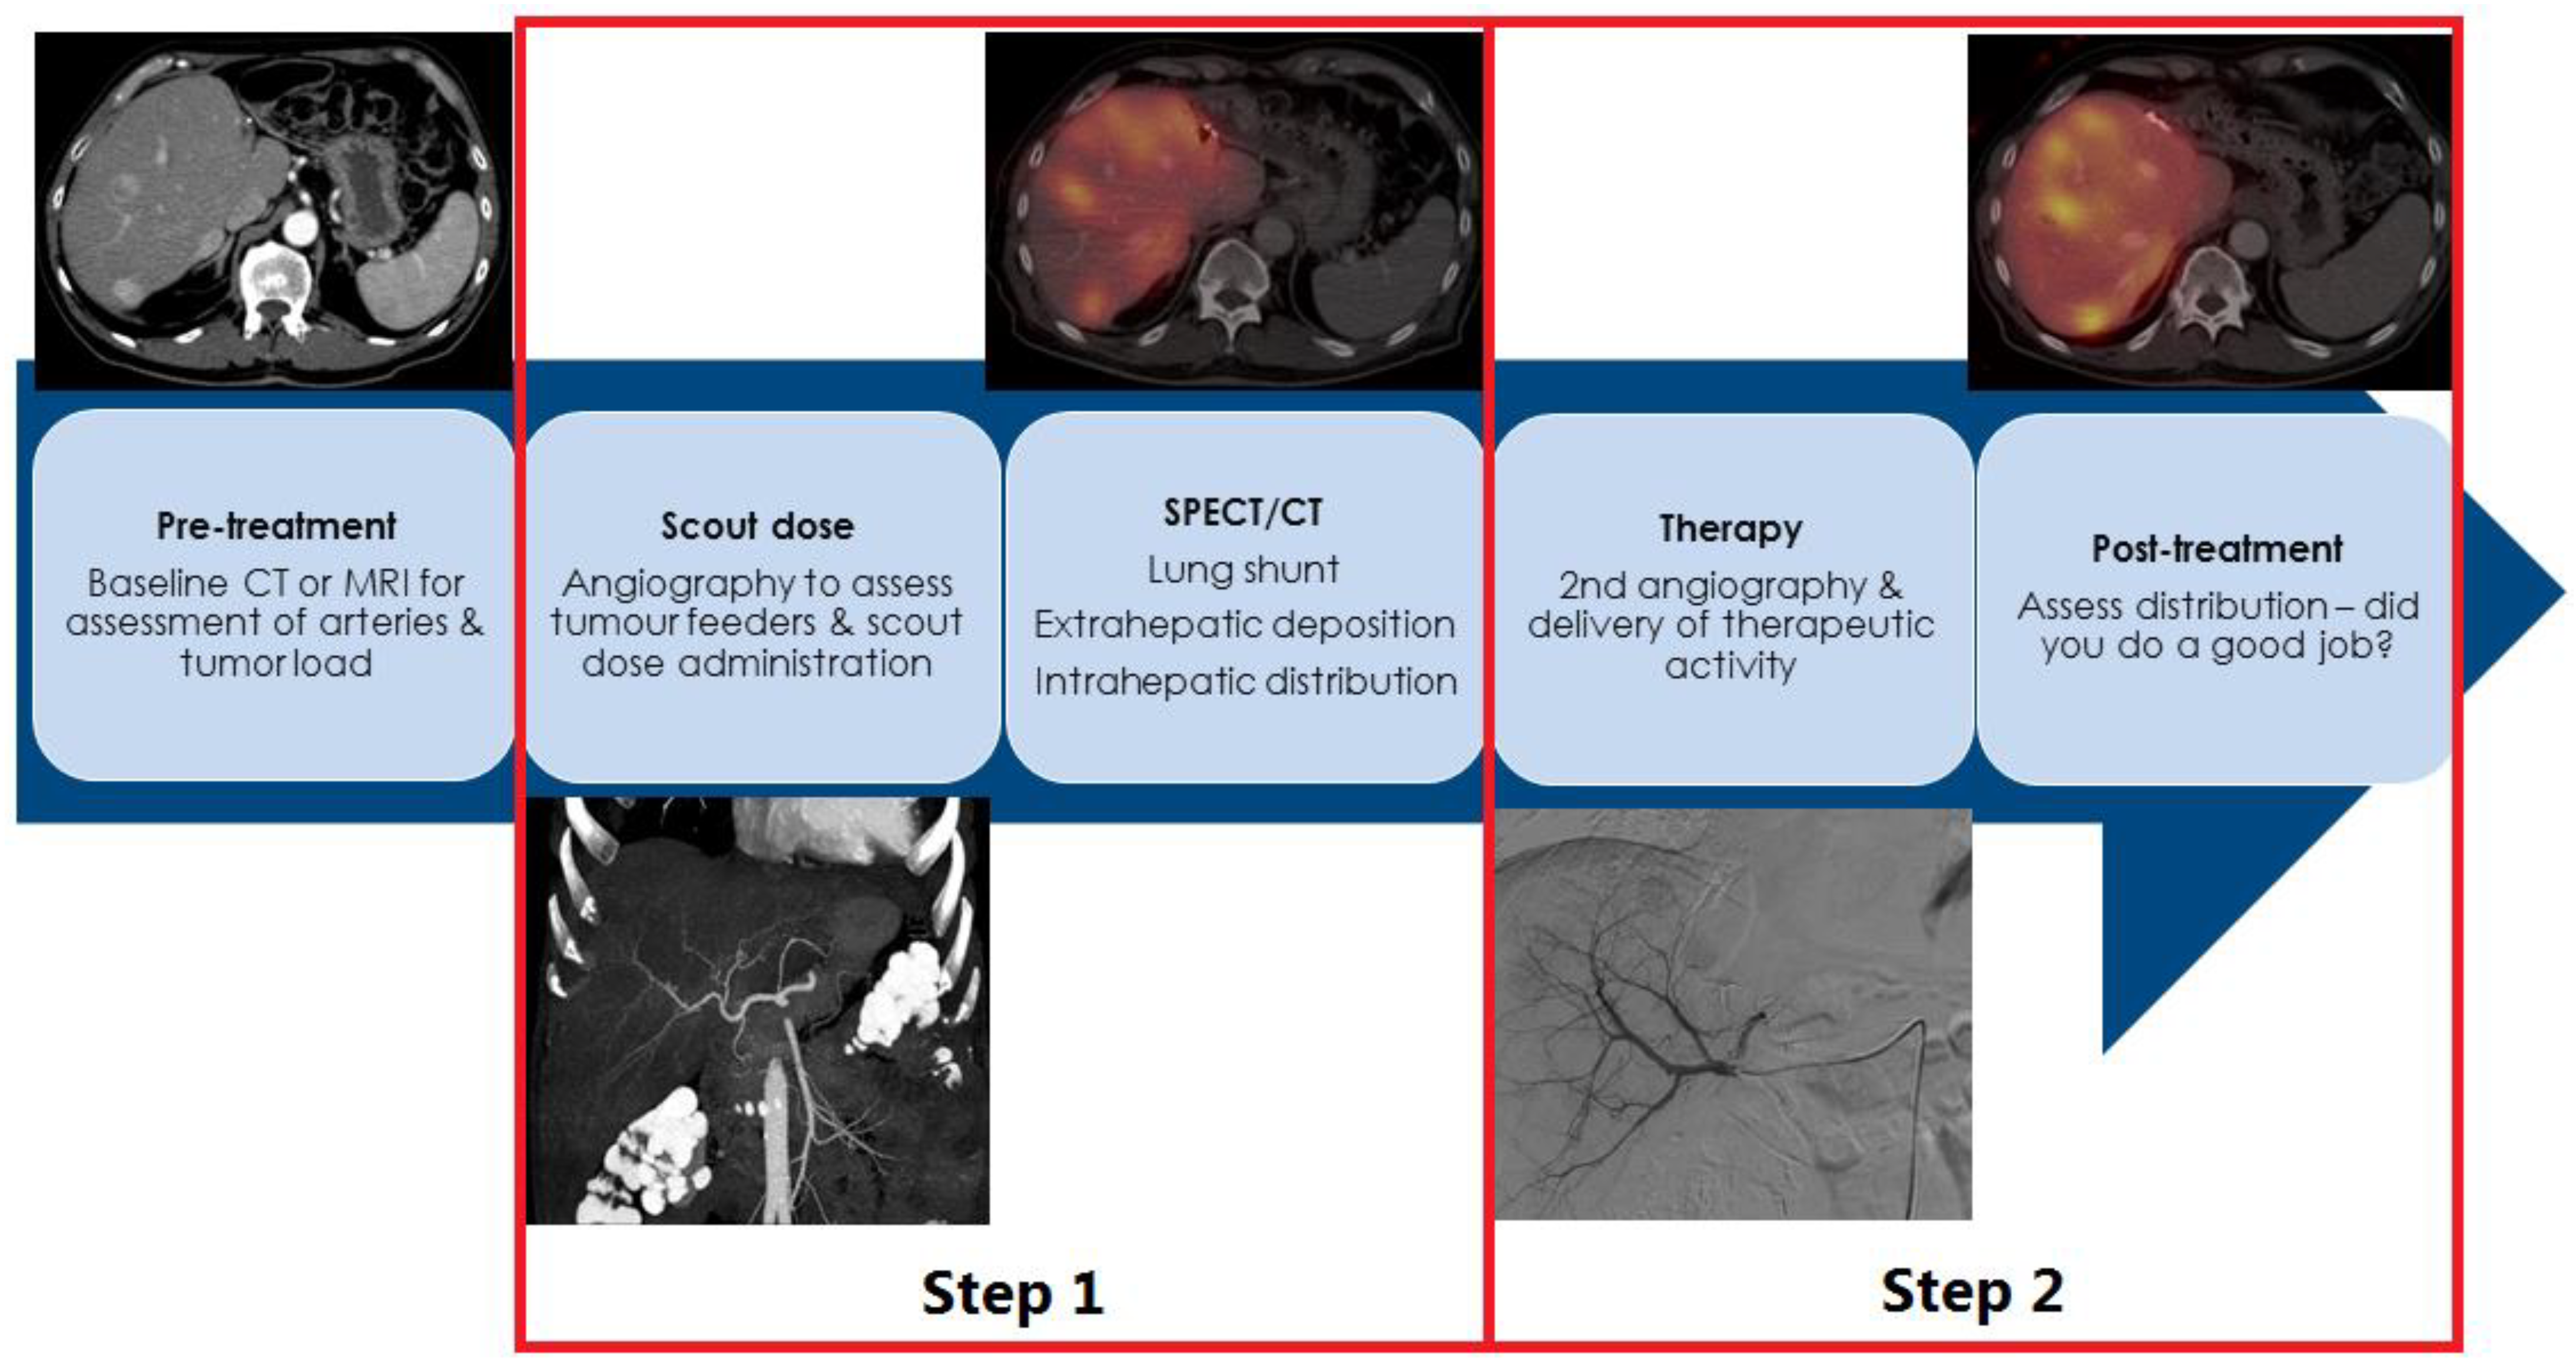

2. How Is Radioembolization Performed?